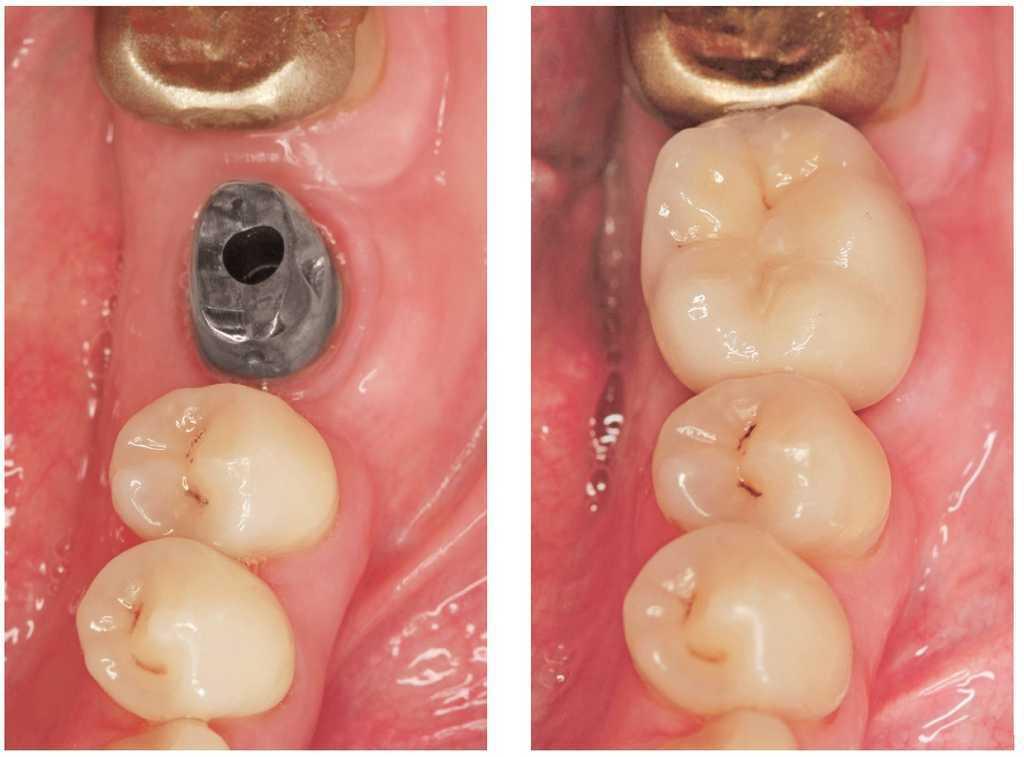

Figura 6a. Implante para sustituir al diente 36. Diente 35 sin caries y corona colada en el diente 37.

Figuras 6b y 6c. Implante unitario con pilar (b) y corona individual (c).